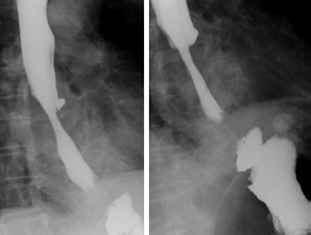

En la radiografía posoperatoria, se observó mejoría de la zona de estenosis y el estómago se encontró dentro del abdomen. En un nuevo esofagograma con bario, se observó paso filiforme del medio de contraste a través de la unión gastroesofágica, lo cual puede considerarse un hallazgo esperable debido a la reducción exitosa del estómago al abdomen, normal en este tipo de procedimientos (figura 5).